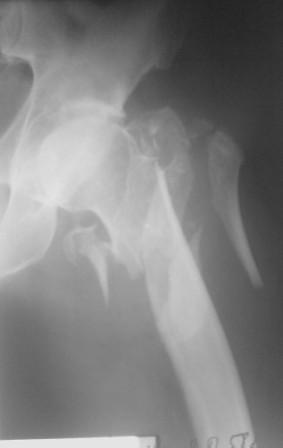

Думаю что перелом всетаки оскольчатый межвертельный, скорее всего использовали бы реконструктивный штифт, но возможно и DHS.

Перелом, на мой взгляд, все-таки чрезподвертельный. Учитывая оскольчатый характер перелома вертельной области, вполне можно рассматривать в качестве альтернативы остеосинтез фиксатором с угловой стабильностью (блокируемая пластина для дистального конца контрлатеральной бедренной кости, производство Синтез или аналог). Конечно, срок ходьбы на костылях будет подольше. Зато картинка посимпатичнее.

По нашему мнению линия перелома проходит вверху через латеральный отдел шейки бедра, вертельная область состоит из нескольких фрагментов. В таких условиях применить DHS или дистальную бедренную пластину LCP представляется нам сомнительным. Закрытый остеосинтез проксимальным гамма-гвоздем или PFNa невозможен т.к. нет ЭОПа.

Прилагаю Р-ы на вытяжении.